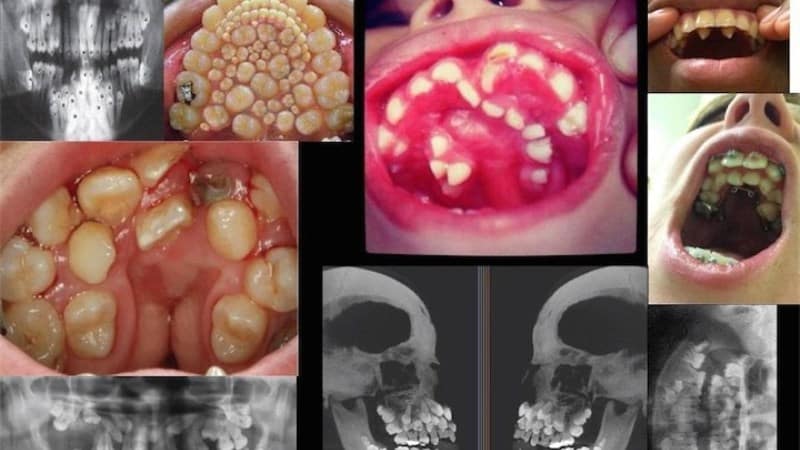

Существует несколько типов гипердонтии, как показано на изображении:

- шиловидные зубы формируются рядом с боковыми и центральными резцами на верхней челюсти. Они имеют острую конусообразную форму и могут выглядеть неэстетично. Кроме того, такие зубы могут причинить значительный вред слизистой оболочке рта;

- парамоляры располагаются рядом с обычными молярами в области щек;

- клыки могут появляться в верхнем ряду зубов;

- премоляры могут развиваться в нижнем ряду.

Клыки и премоляры часто формируются в глубоких и труднодоступных участках. Для диагностики таких случаев обычно требуется рентгенологическое исследование.

Заболевание, при котором в ротовой полости присутствует множество зубов, как на изображении, чаще всего выявляется у людей с постоянными зубами, чем у тех, у кого еще молочные. Дистопированные зубы представляют собой дополнительные элементы, которые формируются вне своего естественного положения. Они могут расти в области неба и на лингвальной стороне десен.